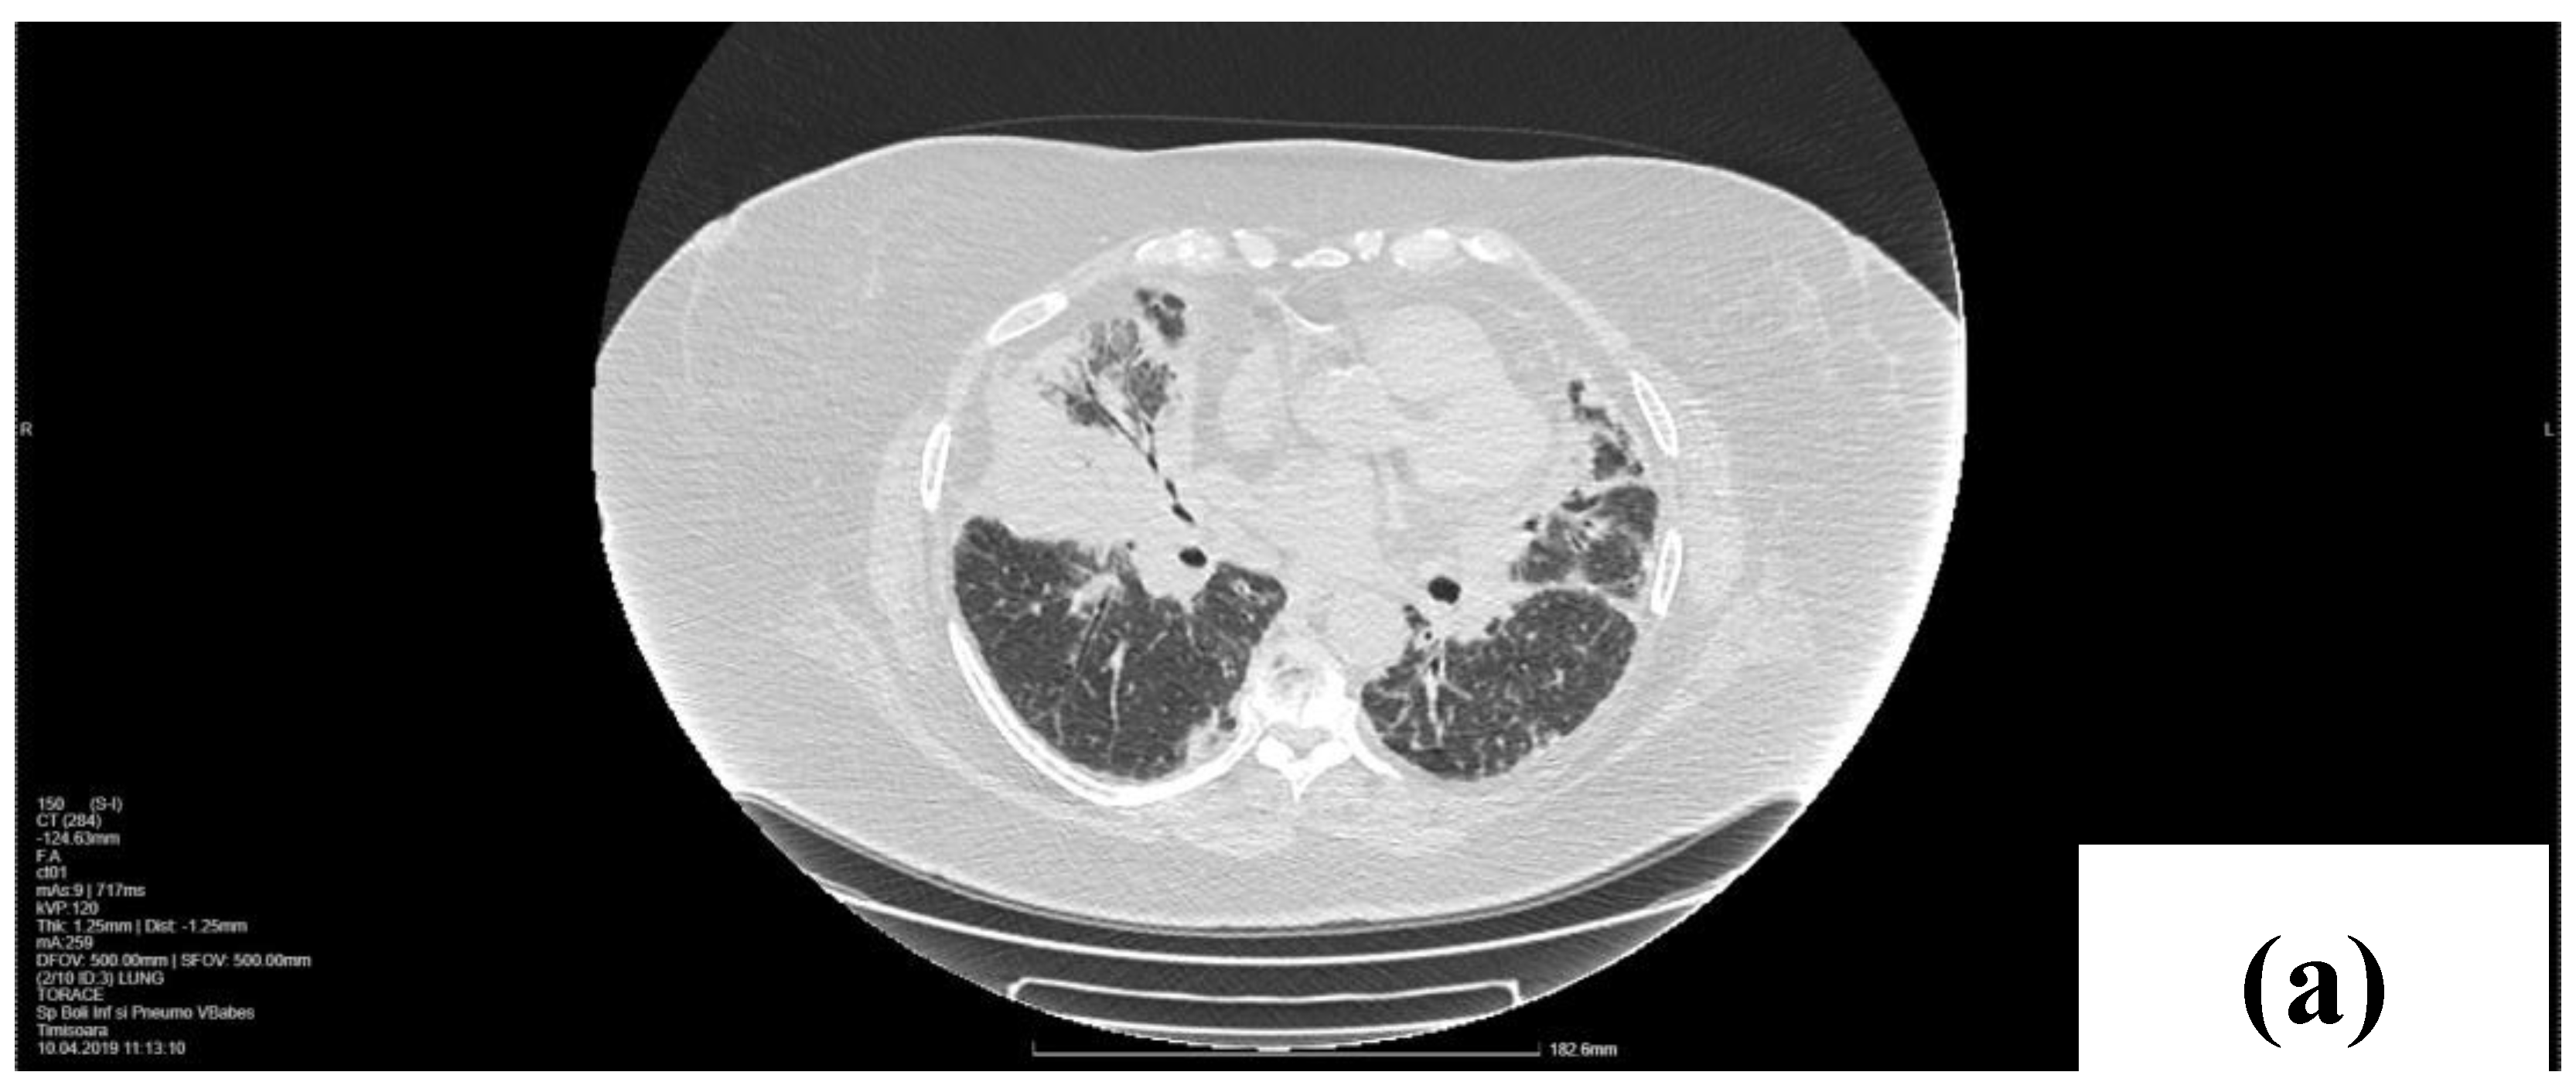

2.1. Laboratory, Radiological, and Histological Examinations